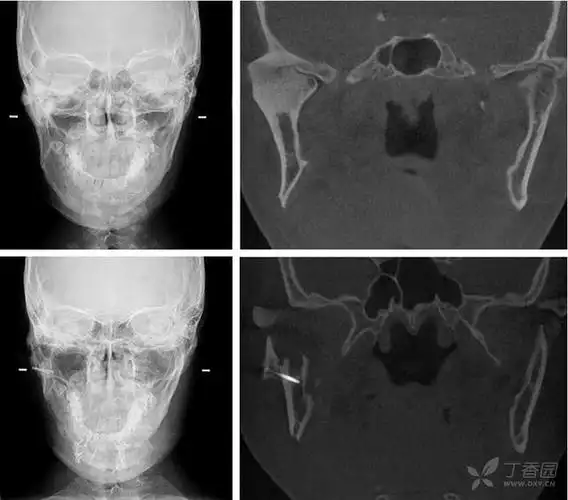

双侧颞颌关节强直

颞下颌关节患者实例